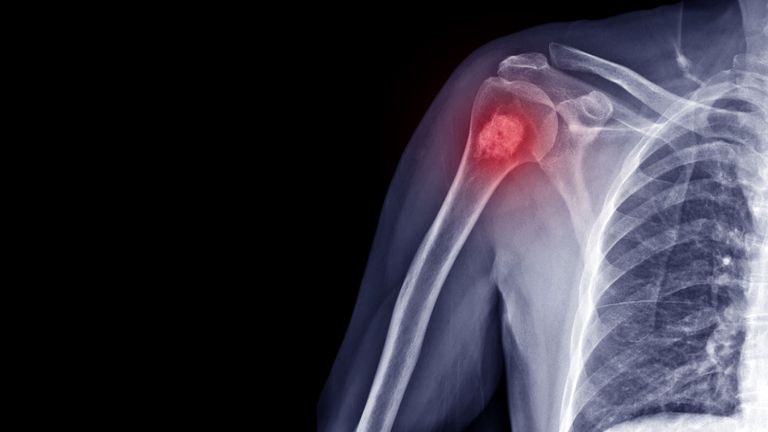

علاج جديد لسرطان العظام يحقق نسب شفاء مرتفعة دون آثار جانبية

طور باحثون من جامعتي إيست أنجليا وشيفيلد دواء جديدا يمكنه محاربة الأنواع الرئيسية من سرطان العظام الأولي، وهو نوع نادر يصيب غالبا الأطفال والشباب.

وسرطان العظام الذي يبدأ في العظام وليس الذي ينتشر إليها يُعتبر من أصعب الأنواع علاجا، حيث يخضع المرضى للعلاج الكيميائي القاسي وعمليات بتر الأطراف، مما يسبب إعاقات مدى الحياة، ومع ذلك، فإن معدلات النجاة بعد 5 سنوات لا تزال منخفضة جدا وتبلغ 42% فقط.